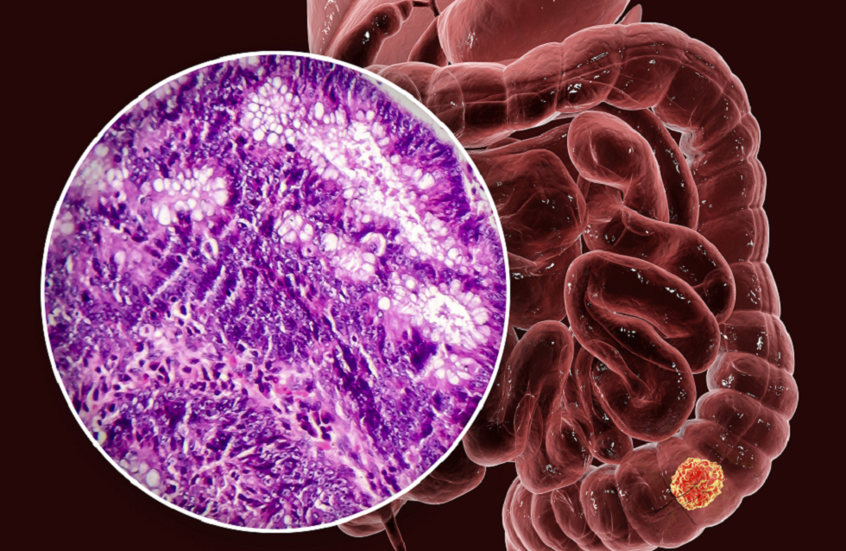

تقنية تصوير جديدة تكشف منطقة الدماغ الأكثر تضررا من "كوفيد-19"

وجدت دراسة جديدة تستخدم تقنية تصوير بالرنين المغناطيسي مبتكرة منطقة الدماغ الأكثر عرضة للإصابة بعدوى "كوفيد-19".

وقالت الدراسة التي أجراها معهد روتمان للأبحاث ومستشفى صنيبروك في تورنتو بكندا إن النتائج الجديدة تعزز فكرة أن "كوفيد-19" يمكن أن يؤدي إلى تغييرات في الدماغ.

حل لغز وظيفة منطقة دماغية ظلت محيرة للعلماء نحو 100 عام

وتم تطوير تقنية التصوير الجديدة والتي تسمى التصوير بالانتشار المترابط (CDI)، بواسطة ألكسندر وونغ، أستاذ هندسة تصميم الأنظمة في جامعة واترلو، كندا.

وأشارت الدراسة المنشورة في دورية Human Brain Mapping إن الشكل الجديد من التصوير بالرنين المغناطيسي، يمكن أن يبرز بشكل أفضل الاختلافات في الطريقة التي تتحرك بها جزيئات الماء في الأنسجة عن طريق التقاط وخلط إشارات التصوير بالرنين المغناطيسي في نقاط قوة وتوقيتات نبض متدرجة مختلفة.

وطور وونغ سابقا تقنية CDI كإجراء تصوير أفضل للكشف عن السرطان.

وكشف تصوير CDI للمادة البيضاء في الفص الجبهي عن انتشار أقل تقييدا لجزيئات الماء في مرضى "كوفيد-19". وفي الوقت نفسه، أظهر انتشارا أكثر تقييدا لجزيئات الماء في المخيخ للمرضى المصابين بـ"كوفيد-19".

وقال وونغ: "قد يعتقد البعض أن كوفيد-19 يؤثر على الرئتين فقط. ما تم العثور عليه هو أن تقنية التصوير بالرنين المغناطيسي الجديدة التي أنشأناها جيدة جدا في تحديد التغييرات التي تطرأ على الدماغ بسبب كوفيد-19. يغير كوفيد المادة البيضاء في الدماغ".

ويشير وونغ إلى أن الدراسة كشفت عن نتيجتين رئيسيتين: أولا، قد يكون المخيخ البشري أكثر عرضة للإصابة بعدوى "كوفيد-19". ثانيا، تعزز الدراسة فكرة أن عدوى "كوفيد-19" يمكن أن تؤدي إلى تغييرات في الدماغ.

وبالإضافة إلى كونها واحدة من الدراسات القليلة التي تُظهر تأثيرات "كوفيد-19" على الدماغ، قال الفريق إنها أول من أبلغ عن تشوهات انتشار في المادة البيضاء في المخيخ.

وبينما صُممت الدراسة في الأصل لإظهار التغييرات التي تطرأ على الدماغ جراء "كوفيد-19"، بدلا من الضرر المحدد، وقالت إن العديد من المصادر المحتملة لمثل هذه التغييرات مرتبطة بالمرض والضرر.

واقترح وونغ أن الاختبارات المستقبلية يمكن أن تركز على ما إذا كان "كوفيد-19" يضر بالفعل بأنسجة المخ. وقال إن دراسات إضافية يمكن أن تحدد أيضا ما إذا كان "كوفيد-19" يمكن أن يغير المادة الرمادية في الدماغ.

وأضاف وونغ: "نأمل أن يؤدي هذا البحث إلى تشخيص وعلاج أفضل لمرضى كوفيد-19".